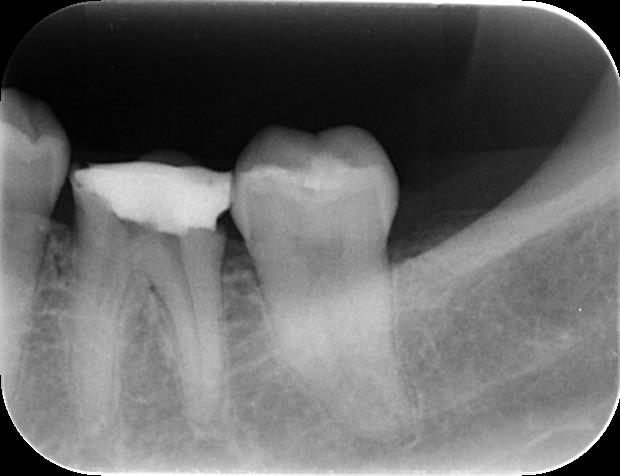

<術前> 他院で5回以上治療したものの、痛みが取れないため来院されました。

<術後>1回目の治療で症状がなくなり、2回目に根管充填し終了。根の先端までピッタリ緊密に充填されていますね。